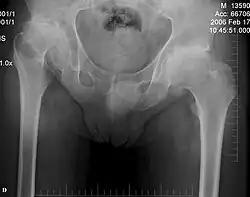

For hip dysplasia, which is currently believed to be epiphyseal in origin, various treatment options and surgical procedures have been explored, including realignment of the proximal femur and/or acetabulum, realignment osteotomy, cheilectomy, and in more advanced cases, total hip replacement (THA).[2][7] However, studies suggest that osteotomies, including femoral and pelvic osteotomies, often fail to prevent the progression of hip subluxation and femoral head migration and may lead to progressive degeneration of the hip joint.[1][7][8]

Regardless of the method used to treat hip dislocation and avoid further joint damage, it appears to progress into complete hip degeneration over time.[7]